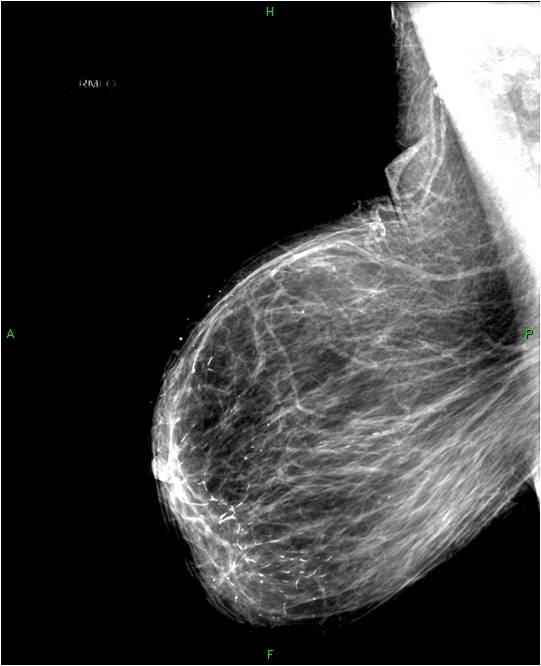

2. Digital mammography has displaced the analogue technic for today almost everywhere: (pictures 1,2,3) phosphorous plate or direct digital methods. For breast imaging the latter is the method of choice. Phases of image production separate. The image is produced on the detectors, but appears on the high resolution monitor and can be stored as a digital data set at various storage mediums (e.g.: CD, hard disk drives).

Image

Picture 1.

Picture 2.

Picture 3.

Mammography exposition: all breast images have to be acquired at least in two directions!

Standard images: cranio-caudal (CC), half-oblique, medio-lateral oblique (MLO).

Additional images: lateral (medio-lateral, latero-medial) magnified images etc.